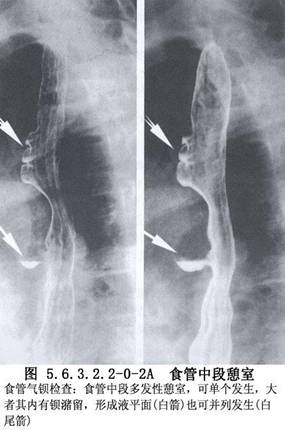

食管中段憩室的诊断主要依靠食管钡餐造影检查和内镜检查。在做钡餐造影检查时,患者取头低脚高位或俯卧位,或取左侧卧位,憩室的位置和轮廓容易显示。必要时做食管CT检查和食管功能测定,以除外其他较严重的疾病。如果出现慢性肺化脓症的症状,则有必要做气管镜检查和肺CT扫描,以明确肺部病变的范围。如怀疑有憩室-支气管瘘,须做支气管碘油造影或气管镜检查;内镜检查有助于发现瘘口。嘱患者口服亚甲蓝或其他染料,若在痰中发现蓝色,即可以确诊(图5.6.3.2.2-0-1~5.6.3.2.2-0-4)。